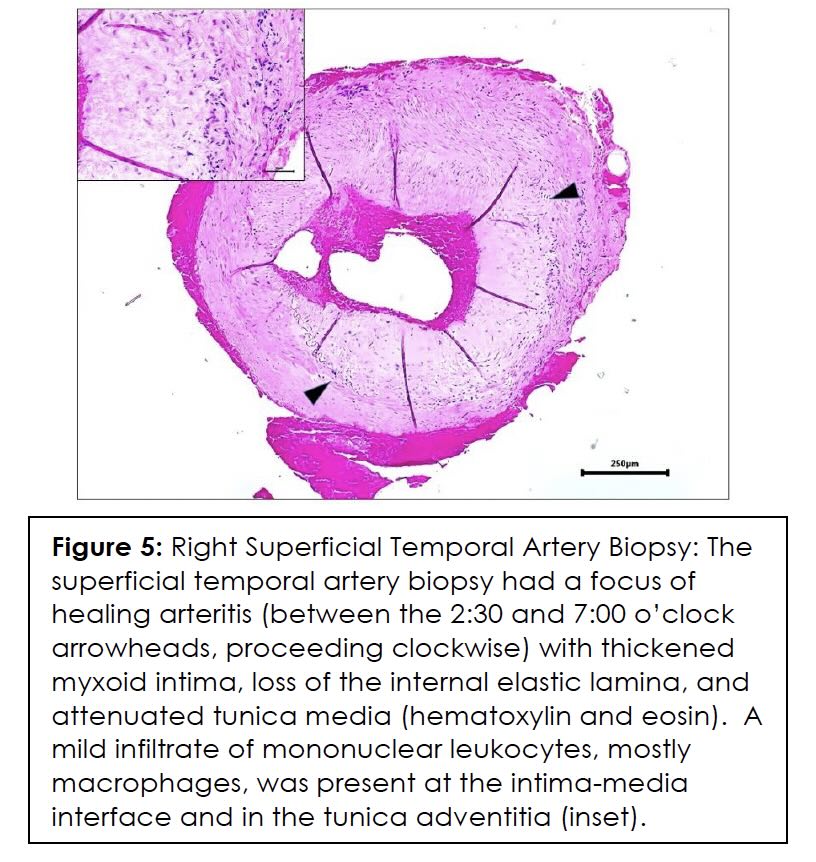

In July 2023, he reported intensification of the pain over the left temple in addition to the right. Repeated ESR, CRP, and temporal artery ultrasound tests were unremarkable. Follow-up physical examination revealed a firmer, tender right temporal artery. Patient was prescribed Prednisone 40 mg for four days due to the suspicion for GCA and a temporal artery biopsy was ordered. He underwent a bilateral temporal artery biopsy which is considered the gold standard for diagnosis of GCA, five days after completing the prednisone 40 mg. The superficial temporal artery biopsy demonstrated healing arteritis and he was started on prednisone 60 mg daily by the Ophthalmologist. With the high doses of prednisone, the temporal headaches became mild, but he continued to experience daily holocephalic headaches, blurred vision, photophobia, and phonophobia. Multiple medications were used for both prevention and acute treatment of his post-concussive headaches with migrainous features, including verapamil, propranolol, sumatriptan, rizatriptan, naratriptan, venlafaxine, and meclizine with inadequate response.

ESR, CRP, and color Doppler ultrasound (CDUS) of his temporal artery in July 2023 were negative, showing no GCA in the superficial temporal arteries. CDUS of bilateral temporal arteries demonstrated normal flow characteristics (Figures 1,2,3,4). Physical examination and temporal predominance of headache prompted obtaining the temporal artery biopsy in August 2023, which revealed healing GCA (Figure 5). The presence of myxoid change in the asymmetrically thickened intima and a residual infiltrate of mostly macrophages at the tunica intima-tunica media interface where the internal elastic lamina was absent allowed distinction of healing arteritis from age-related histopathological change, which may resemble healed giant cell arteritis. 3